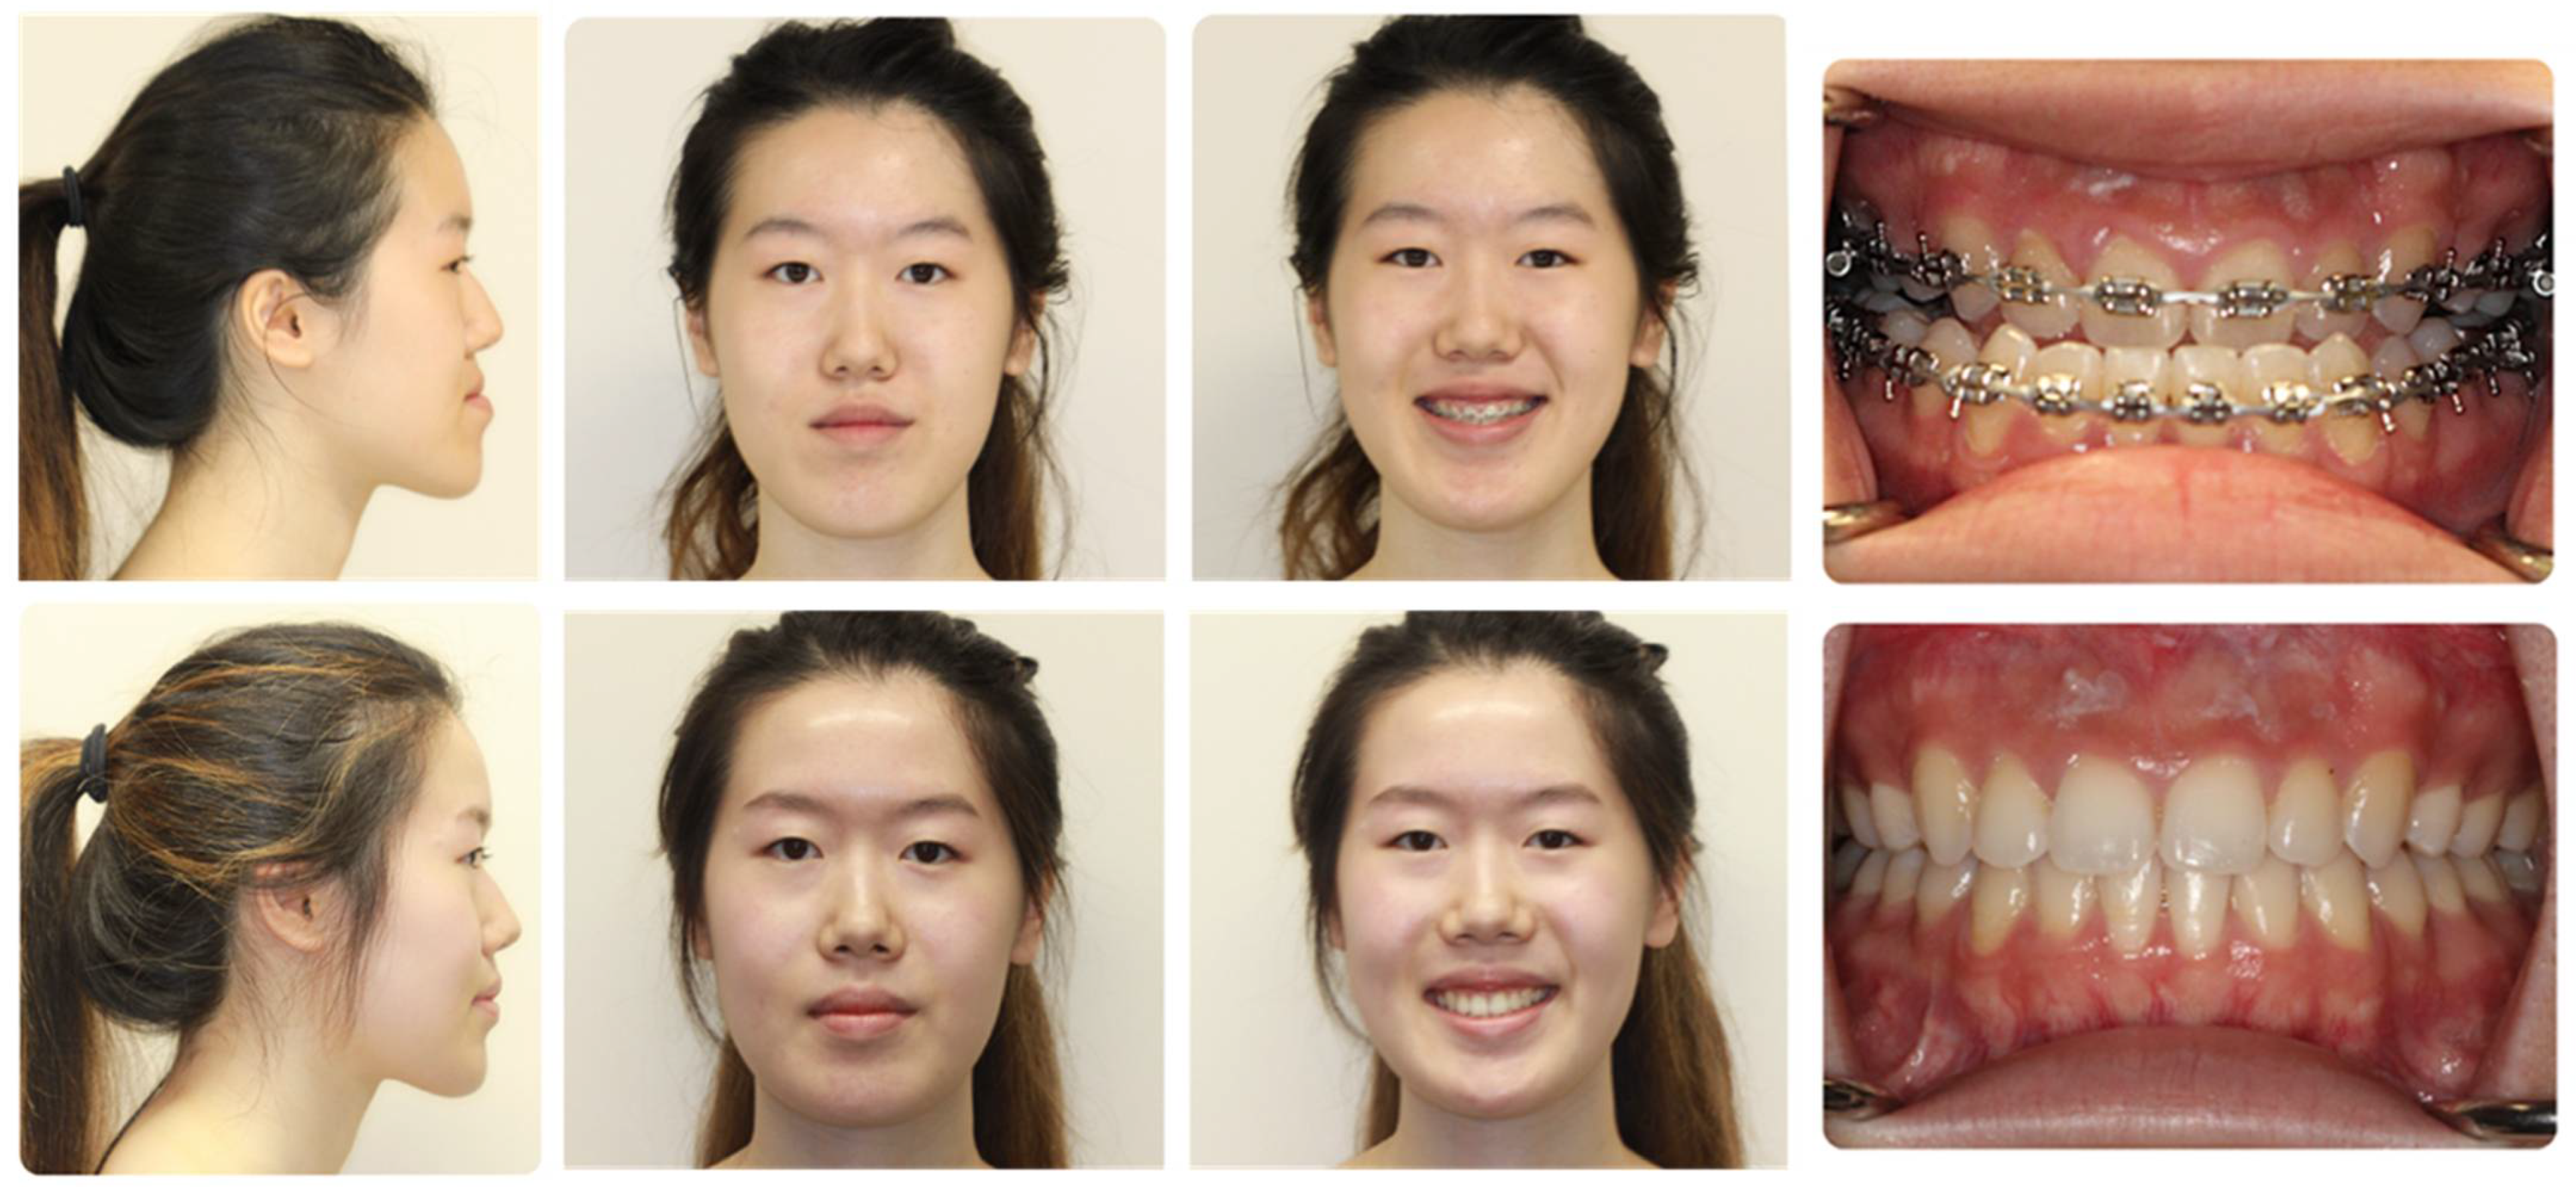

3.4. Clear Aligner Therapy (Figure 7)

- Liou, Y.J.; Chen, P.R.; Tsai, T.Y.; Lin, S.; Chou, P.Y.; Lo, C.M.; Chen, Y.R. Comparative assessment of orthodontic and aesthetic outcomes after orthognathic surgery with clear aligner or fixed appliance therapy. Plast. Reconstr. Surg. 2023. [CrossRef]

- Parsaei, Y.; Uribe, F.; Steinbacher, D.M. Clear aligner therapy and orthognathic surgery. J. Clin. Orthod. 2022, 56, 692–707. [Google Scholar] [PubMed]

- Kankam, H.; Madari, S.; Sawh-Martinez, R.; Bruckman, K.C.; Steinbacher, D.M. Comparing Outcomes in Orthognathic Surgery Using Clear Aligners versus Conventional Fixed Appliances. J. Craniofac Surg. 2019, 30, 1488–1491. [Google Scholar] [CrossRef]

- Kankam, H.K.N.; Gupta, H.; Sawh-Martinez, R.; Steinbacher, D.M. Segmental Multiple-Jaw Surgery without Orthodontia: Clear Aligners Alone. Plast. Reconstr. Surg. 2018, 142, 181–184. [Google Scholar] [CrossRef]